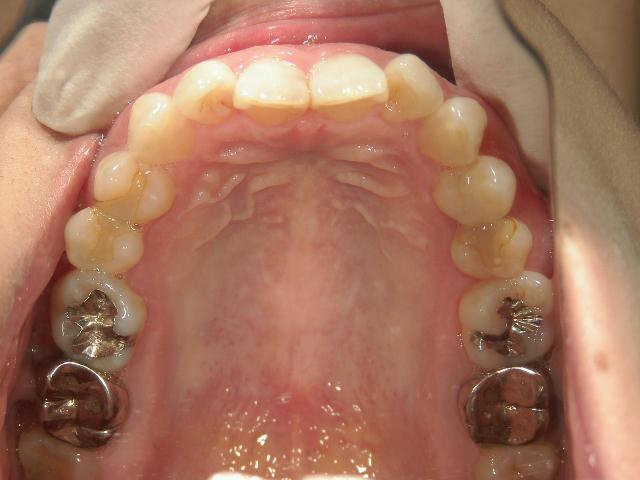

矯正歯科 治療前

全顎ワイヤー矯正 症例(2)

36歳女性 磐田市

在住

治療期間2年6

ヶ月